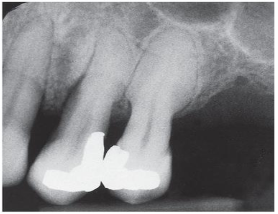

Observe a radiografia periapical a seguir.

HUPP, James R.; III, Edward E.; TUCKER, Myron R. Cirurgia Oral e Maxilofacial Contemporânea. Grupo GEN, 2021. E-book. ISBN 9788595157910.

De acordo com a imagem, qual é o diagnóstico mais provável para esse caso?